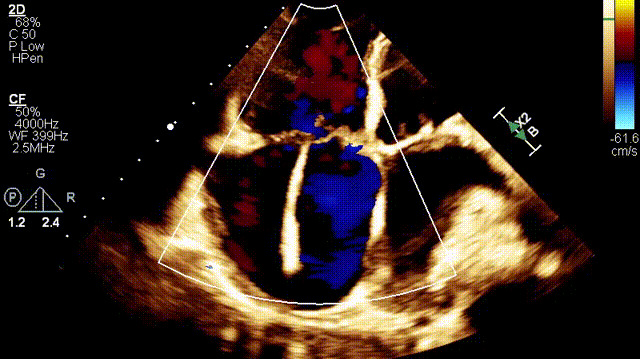

接受治療的是一例89歲的超高齡女性患者,主訴“起搏器術(shù)后7年余,反復(fù)氣促4年”,因反復(fù)心衰失代償,胸腔積液就診。術(shù)前超聲提示:1.雙房及右室擴(kuò)大(右室舒張末和收縮末容積分別為55ml和21ml,右室FAC27%);2.三尖瓣瓣環(huán)擴(kuò)張(瓣環(huán)左右徑41mm,前葉長(zhǎng)度21.3mm,隔葉長(zhǎng)度15.2mm,后葉長(zhǎng)度23.1mm),瓣葉閉合不攏;3.功能性重度三尖瓣反流(FTR 5+,收縮期三尖瓣口反流束縮流頸寬度21mm);4.下腔靜脈內(nèi)徑約25mm,呼吸塌陷率<50%;5.輕度肺高壓。術(shù)前CT結(jié)果顯示,入路血管最小平均徑約9.6mm,入路血管無(wú)嚴(yán)重迂曲、鈣化。隨后,王焱教授及其團(tuán)隊(duì)王斌教授、陳翔教授、超聲科蘇茂龍主任、手術(shù)室溫紅梅護(hù)士長(zhǎng)進(jìn)行了詳細(xì)而周密的術(shù)前討論,最終選擇我國(guó)自主研發(fā)的LuX-Valve Plus經(jīng)血管三尖瓣置換系統(tǒng)對(duì)患者進(jìn)行手術(shù)。

植入前DSA

植入前超聲

手術(shù)在全麻狀態(tài)下開(kāi)展,此次手術(shù)采用經(jīng)右側(cè)頸靜脈入路的方式將輸送器送入患者心臟內(nèi),在TEE及DSA引導(dǎo)下調(diào)整輸送器頭端角度,使得輸送器與三尖瓣瓣環(huán)平面垂直。在輸送器進(jìn)入右心室后釋放室間隔錨定裝置,而后釋放瓣葉夾持件(2個(gè)耳片結(jié)構(gòu))成垂直狀態(tài)。在TEE及DSA確定夾持件固定至三尖瓣葉根部且位于右室側(cè)后釋放人工瓣心房側(cè)盤(pán)片。隨后調(diào)整瓣膜同軸性以及室間隔錨定件位置(貼合室間隔),前推藏針管并固定,進(jìn)而釋放室間隔錨定裝置,并再次確認(rèn)瓣膜位置、穩(wěn)定性及同軸性,合攏輸送鞘后撤出輸送器,完成LuX-Valve Plus人工三尖瓣瓣膜的植入。